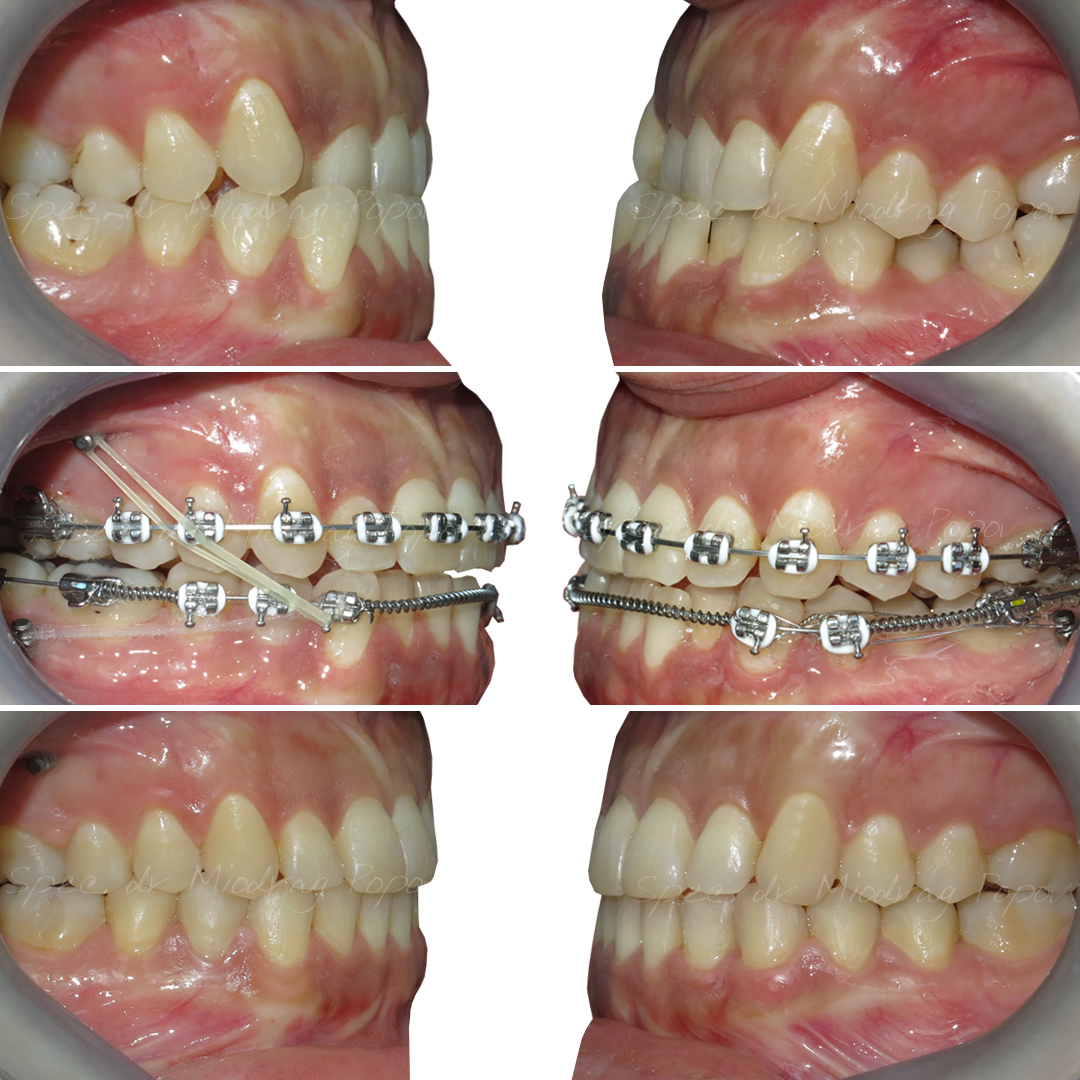

Jedan od naših top slučajeva iz 2024. godine!

Uz pomoć mini implantata uspeli smo da rešimo sledeće nepravilnosti kod pacijenta:

- 1/2 III klasa obrnutim prekolopom gornjih frontalnih zuba

- Teskoba u gornjem i donjem zubnom nizu

- Neusaglašene sredine zubnih nizova

- Jednostrano ukršten zagrižaj

Preciznost i stabilnost koje pružaju mini implanti omogućile su nam vrhunski rezultat!